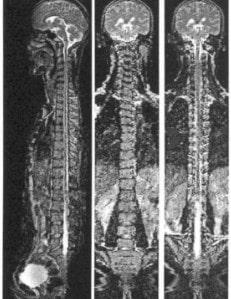

Diagnóstico de espondilosis

Diagnostico médico de la Espondilosis

El diagnóstico primario de espondilosis comienza con un examen en el consultorio de un neurólogo. De acuerdo con los resultados, el médico puede prescribir una prueba de mayor precisión.

Los rayos X pueden revelar la presencia de osteofitos y una disminución en la altura de los discos intervertebrales. Pero la tomografía computarizada (TC) y la imagen de resonancia magnética (IRM), son más precisas.

Con la TC se puede detectar cambios en los huesos asociados con la espondilosis. La IRM permite detectar anomalías de los discos, los ligamentos y los nervios.